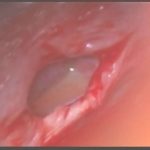

術中写真

摘出 後